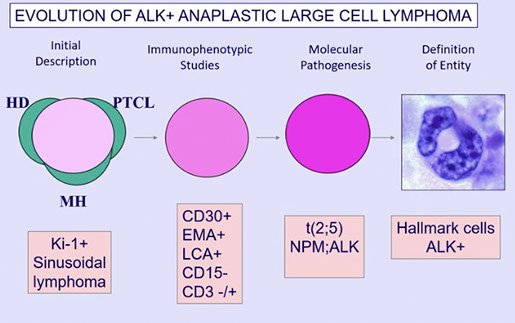

Anaplastic large cell lymphoma (ALCL), ALK positive

Anaplastic large cell lymphoma (ALCL), ALK negative